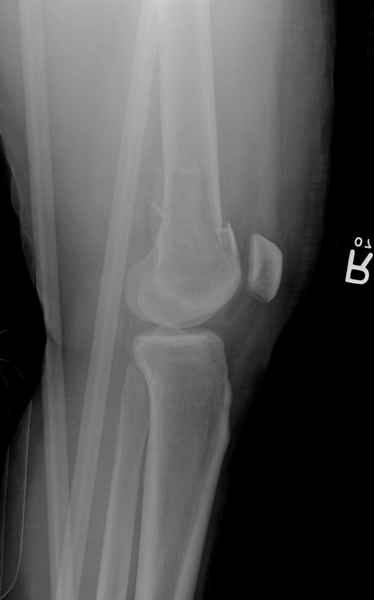

Re: Сегментарный перелом бедра - открыто или закрыто?

При наличии различных имплантов, любые варианты: слева (полу) открытым - мининвазивным, а справа закрытым интрамедуллярным методом, его считаем более чем приемлемым для фиксации данных переломов.

Проксимальная и дистальная блокировка, независимо от техники введения штифта, ретроградно или антеградно, гарантирует сращение сегментарных переломов бедра без укорочения. Штифты диаметром 12 мм с блокировкой сверху и вниз двумя шурупами выдерживают вес 75 кг больного, что позволяет раннюю профилактику контрактур.

Погоня за "красивой рентгенограммой" не всегда оправдана для фиксации кости, где имеется массивное мягкотканое покрытие. Если так уж хочется исправить положение кости, то при наличии ЭОП, большие костные фрагменты могут быть развернуты или приближены к основному фрагменту методом применения Joystick.

Главное в лечении сегментарных переломов - необходима осторожность при рассверливании канала, продвижение гибкого сверло через сегмент проводят без сверления, толканием, а то были случаи, когда весь сегмент крутился вместе со сверлом.

Из-за вариабельности установки дистальных шурупов и возможности перкутанного введения проксимально предпочитаем DePuy Polyax, хотя на сегодняшнем маркете множеств вариантов фиксации дистального бедра перкутанном методом.